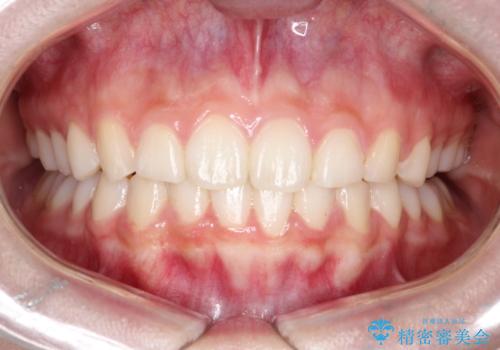

非抜歯矯正では、歯の動きを慎重に調整することが求められます。本症例では、奥歯を遠心に移動させることで、舌側に転移した右下第二小臼歯の位置を改善しました。また、IPRを行うことで歯間スペースを確保し、無理なく歯列の調整を行いました。非抜歯での治療は、特に臼歯関係や正中を保ちながら治療できるというメリットがあり、最終的にはバランスの取れた歯並びを実現できました。審美ワイヤーを使用したことで、治療中も目立ちにくく、患者様の見た目にも配慮した治療を行いました。